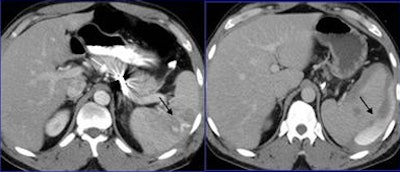

| Although delayed CT scanning was helpful in only 2.8% of patients overall, it was helpful in 20% of solid organ injuries and in 16% of bowel or mesenteric injuries. In patients with an initial CT scan suggesting injury, delayed CT was helpful in 16.6% of cases. |

Overall, delayed CT was useful in just 2.8% (16 of 562) of all patients (95% confidence interval, 1.2-3.5) referred for evaluation following trauma as part of a whole-body CT protocol, Lemos said. But its utility rose to 16.6% (16 of 96; 95% confidence interval, 7.5-19) in patients with injuries detected or those suspected of having injuries after initial CT.